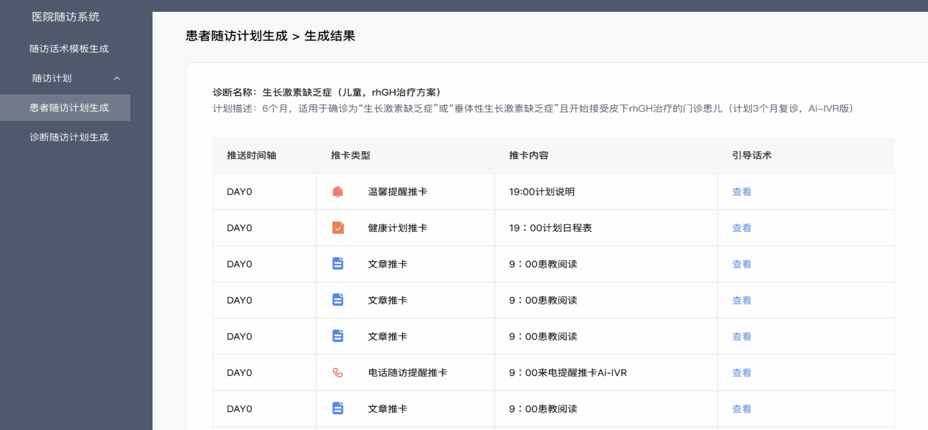

佛山QY球友会禅诚医院AI随访系统